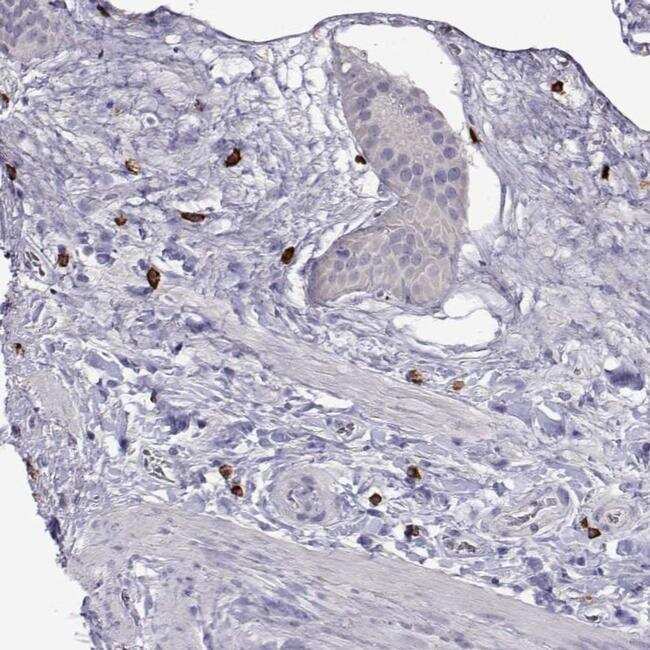

- Immunohistochemical analysis of WDR52 in human gallbladder using WDR52 Polyclonal Antibody (Product # PA5-64321) shows strong positivity in a subset of leukocytes.